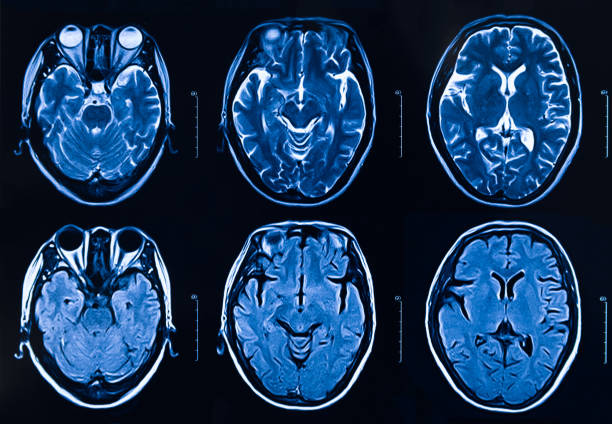

뇌졸중이란

뇌졸중은 뇌경색, 뇌출혈 등 뇌 관련질환을 이르는 전체적인 질병을 나타내는 단어입니다. 개별적으로 살펴보면 뇌경색은 뇌혈관이 막히거나 다른 곳에서 색전물질이 혈관을 통해서 전달이 되어서 혈관이 막힐 때 나타나는 병이며 뇌출혈은 작은 혈관이 파열되어 뇌동맥류 같은 질병들이 있는 상태에서 높은 압력으로 파열되면서 뇌실질에 출혈이 일어나는 경우를 말합니다

따라서, 뇌에 혈액을 공급하는 뇌혈관에 문제가 발생하면 산소, 영양분이 뇌에 제때 제대로 공급 하지 못해 뇌조직과 뇌세포의 기능이 떨어지면서 여러가지 증상이 나타나 골든타임이 중요한 뇌졸중이기 때문에 위에서 언급했듯 전조증상을 미리 잘 알고 있는 것이 중요합니다.